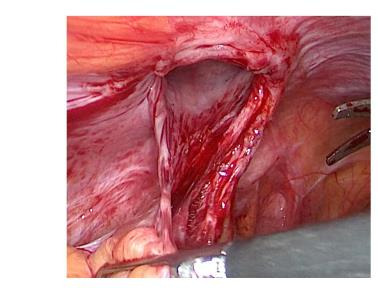

Port-site hernia (PSH) of less than 10 mm is an exceptionally rare complication of minimally invasive surgery (MIS). To date, there have been no cases in the literature reporting recurrence of PSH from a 5 mm incision. We present the first case of PSH recurrence in a woman who underwent surgery for benign gynaecological pathology via a MIS approach. Her post-operative course was complicated by an episode of symptomatic hernia arising from a 5 mm accessory trocar which was surgically managed. A few months later she re-presented with the same symptoms and had a PSH recurrence of the same port-site. Two corrective surgeries employing different techniques were performed. The first episode was managed laparoscopically using interrupted stitches. On the other hand, the PSH recurrence was managed by placement of a mesh. Ultrasound played a crucial role in diagnostics, especially in the recurrent setting. Due to the complete absence of similar cases in the literature, the decision making around the management of a PSH recurrence from a 5 mm trocar site proved to be challenging. As MIS is the current standard of care, more cases are likely to occur, however despite the increasing number of surgical procedures performed via MIS, no established guidelines for managing such complications have been proposed. Trying to bridge this gap, we present the case report of the first case of PSH recurrence from a 5 mm accessory port and a review of the most significant literature available to date. We finally summarise the reported cases of PSH and the types of surgical repair conducted to highlight the absence of a standard of care.